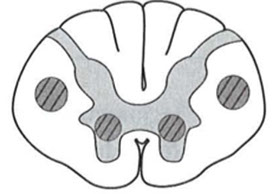

Vitamin B12 - Subacute Combined Degeneration of the Spinal Cord (SCDSC)

Degeneration of lateral and posterior columns and corticospinal tracts of spinal cord.

- Similar to pattern of HIV Myelopathy

SCDSC with degeneration of white matter in posterior and lateral funiculi of the spinal cord. The degenerated fibers lose their myelin and are thus unstained

Subacute Combined Degeneration of the Spinal Cord